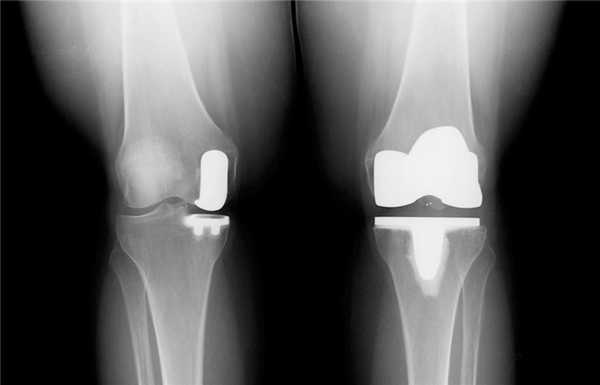

Две техники операции у одного пациента.